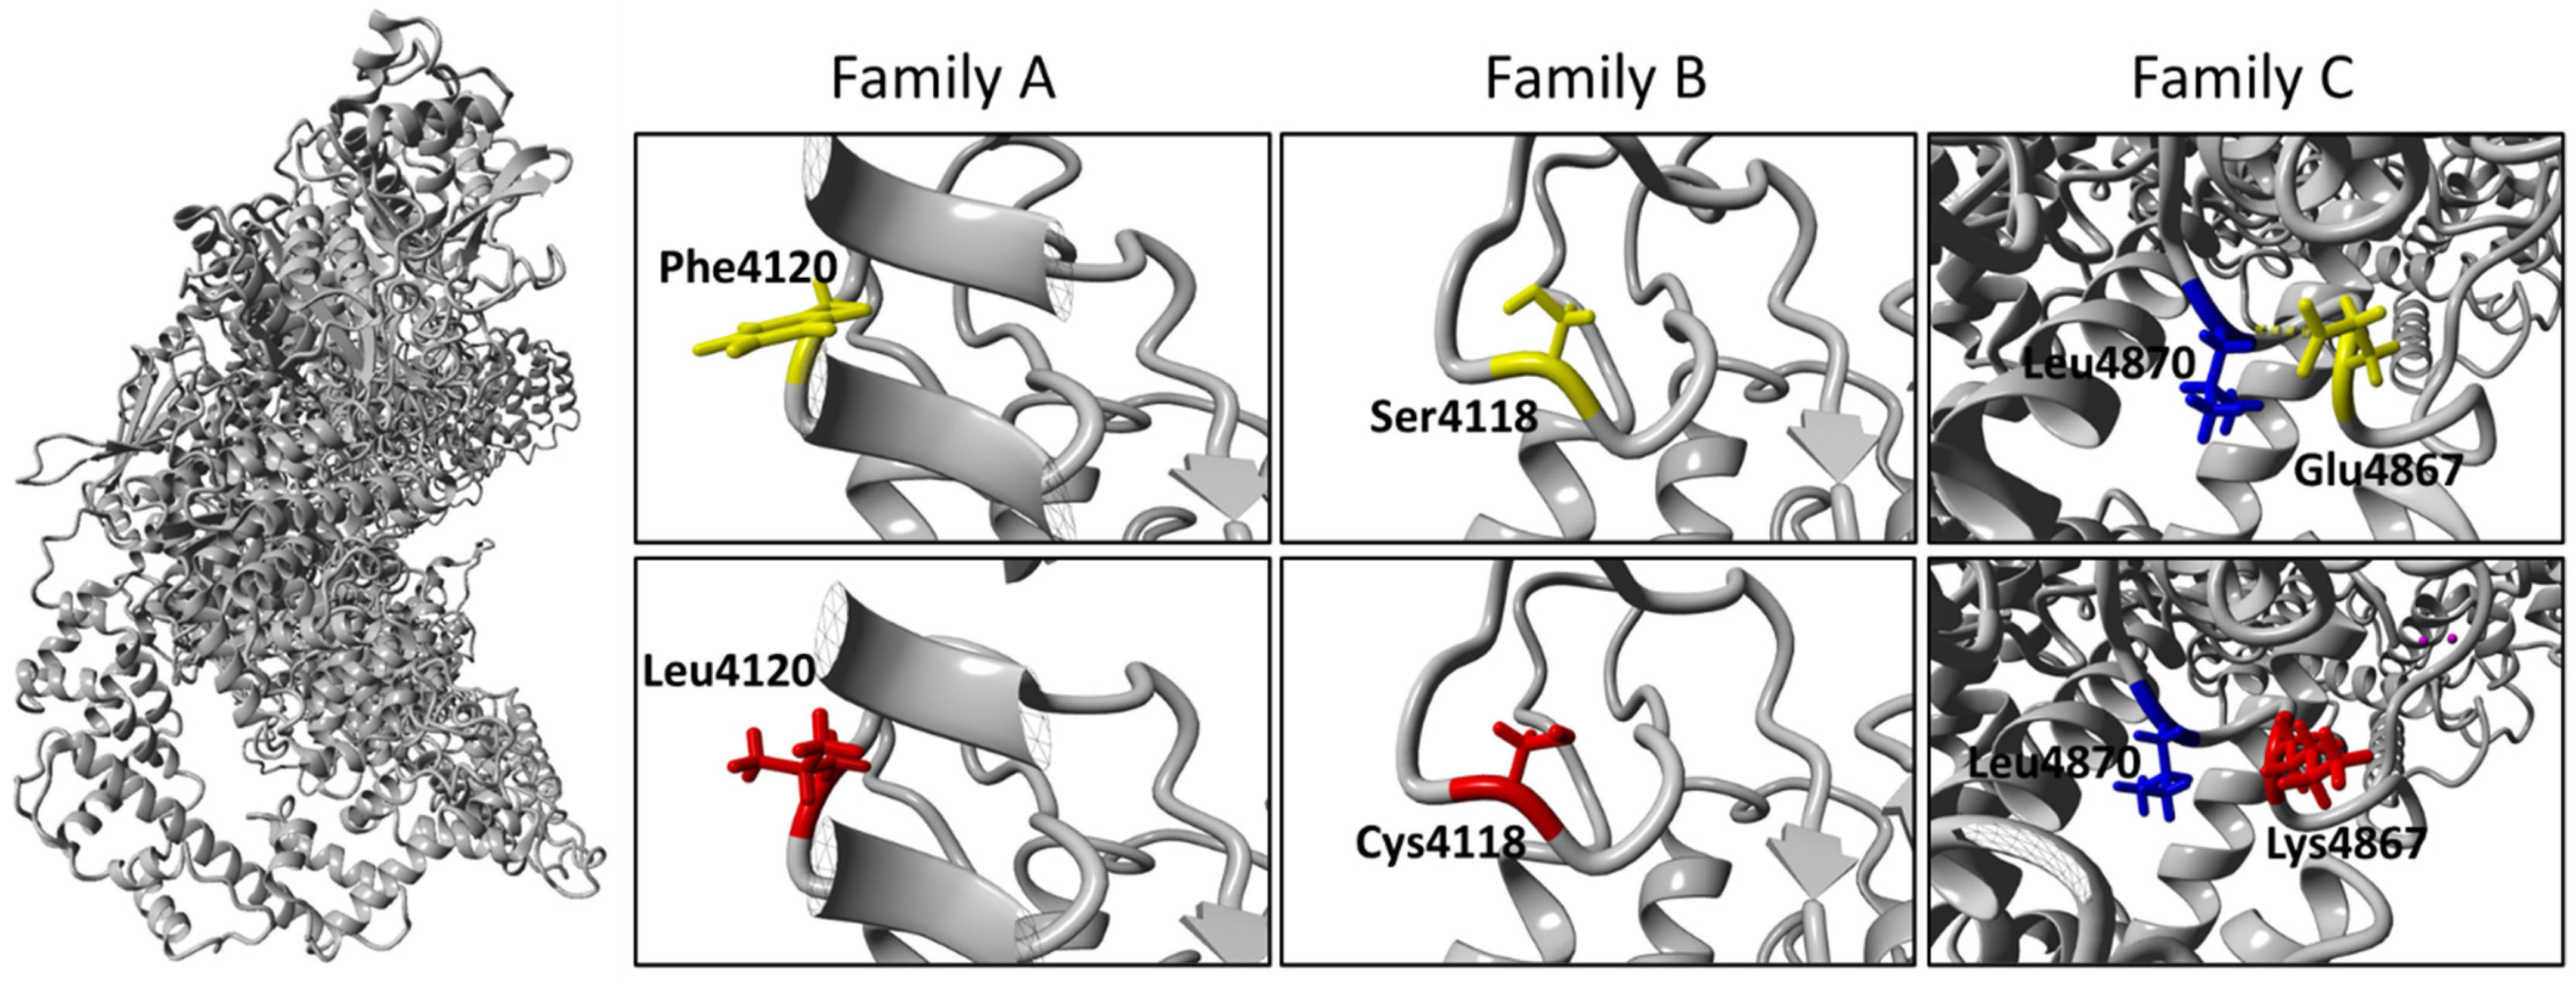

2.4. Molecular Diagnosis